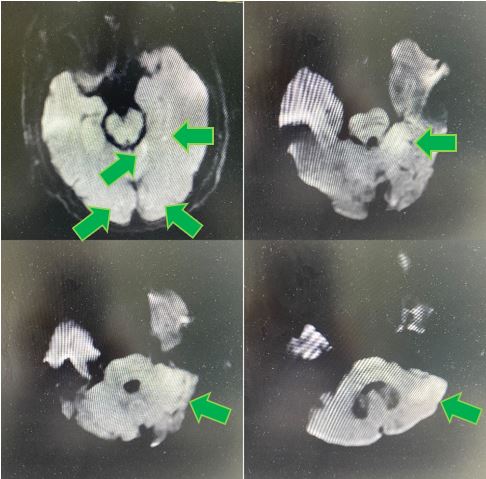

颅脑DWI示左侧小脑半球、左侧颞叶、双侧枕叶急性脑梗死

颅脑MRA示双侧大脑后动脉及双侧小脑上动脉未见显影,基底动脉远端闭塞